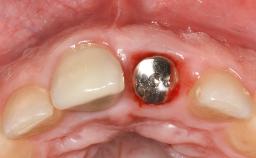

In this case, Myroslav Solonko, Ignacio Sanz Sánchez and Mariano Sanz present a treatment that aims to eliminate exposed implant threads by modifying the implant surface, converting a moderately-rough surface into a smooth surface.

A 63-year-old male patient was referred to the post-graduate periodontal clinic of the Complutense University of Madrid for the treatment of peri-implantitis. According to the patient’s record, all his maxillary teeth had been extracted ten years previously due to severe periodontitis, and a full-mouth implant-supported restoration on eight implants was placed. No supportive periodontal therapy was provided apart from occasional check-ups by the restorative dentist.